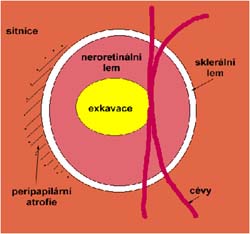

Velikost terče

Tento terč má širokou cirkulární peripapilární atrofii, která opticky vytváří falešný dojem širokého neuroretinálního lemu, zvláště nasálně.

Rozsah a hloubka exkavace

Správně určit rozsah a hloubku exkavace vyžaduje vidět terč prostorově:

Co je příčinou toho, že při pohledu na snímky hodnotíme rozsah exkavace nesprávně? Je to skutečnost, že i růžová oblast neuroretinálního lemu může být již prohloubená, což vídáme zvláště na počátku rozvoje glaukomové neuropathie.

A jak se můžeme vyhnout záměně okrsku bledší barvy za skutečnou exkavaci? Tím, že budeme mít na paměti, že exkavace může být větší než nablednutí. Také zařazení zeleného filtru na pomůže snížit nežádoucí barevný kontrast.

Cévy

Jaké informace nám mohou říci cévy o poškození terče glaukomem? Cévy kopírují povrch terče, jeho nerovnosti se projevují záhyby cév. Při glaukomu mohou být obnaženy cévy, které dříve probíhaly v n. lemu. Při pokročilého glaukomu se zužují arterie a vzniká arteriovenózní nepoměr!

Na dolním pólu terče je patrný zálom vény, která zviditelňuje přítomnost i hloubku exkavace až k dolnímu okraji terče.

V nasálním horním kvadrantu terče vidíme obnažené cévy, které dříve probíhaly v lemu. Toto obnažení může být jedním z prvních příznaků glaukomové neuropathie.